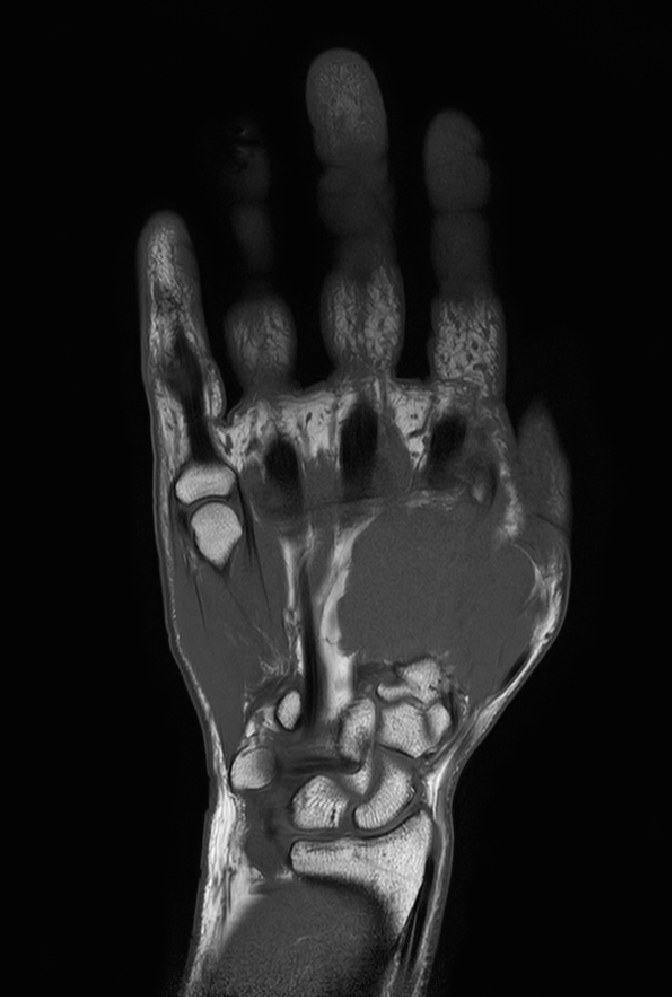

Coronal T1w TSE mDIXON XD (In Phase)